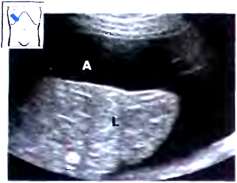

Рис. 12. Ранняя стадия портальной гипертензии. Имеется пограничное расширение воротной вены (PV): 12,9 мм внутри печени, 13,7 мм в печеночно-двенадцатиперстной связке (курсоры). L - печень.